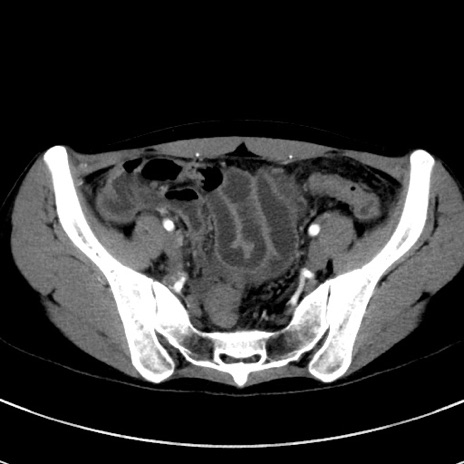

症例17(横断像)

【症例】20歳代女性

【主訴】嘔吐、下腹部痛

【現病歴】昨日夕食後に嘔吐し下腹部痛が出現。本日になっても嘔吐持続し改善しないため来院。

【身体所見】意識清明、BT 37.2℃、BP 108/67mmHg、腹部:平坦、やや硬、下腹部正中から右にかけて圧痛あり、反跳痛軽度あり、tapping pain(+)。

【データ】WBC 13600、CRP 14.94